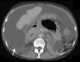

Peritoneal fluid

Peritoneal fluid is a serous fluid made by the peritoneum in the abdominal cavity which lubricates the surface of tissue that lines the abdominal wall and pelvic cavity. It covers most of the organs in the abdomen. [Source: Wikipedia ]